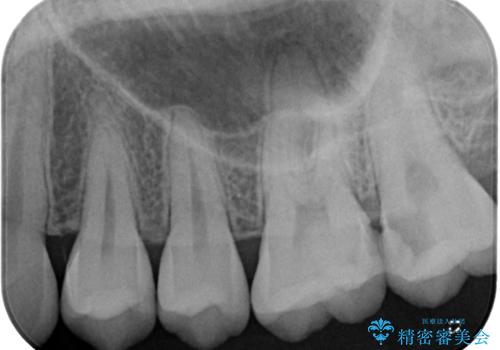

- 奥歯に激痛が走り近医を受診したところ、根管治療が必要とのことで、当院での治療を希望して来院された患者様です。

奥歯2歯の間からむし歯が広がったようで、最後方歯は既に神経が失活している状態で、手前の歯は神経組織に問題はないものの速やかに処置が必要な状態でした。

最後方歯は根管治療を行った上でオールセラミッククラウンにて補綴治療を行うこととし、手前の歯はセラミックインレーにて修復治療を行うこととしました。

今後は定期的にレントゲン写真を撮りながら、根管治療の経過観察を行っていくことになります。